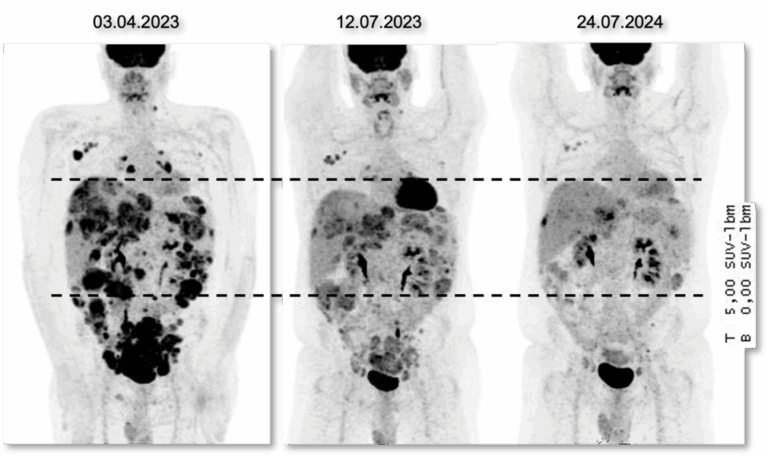

DSRCT